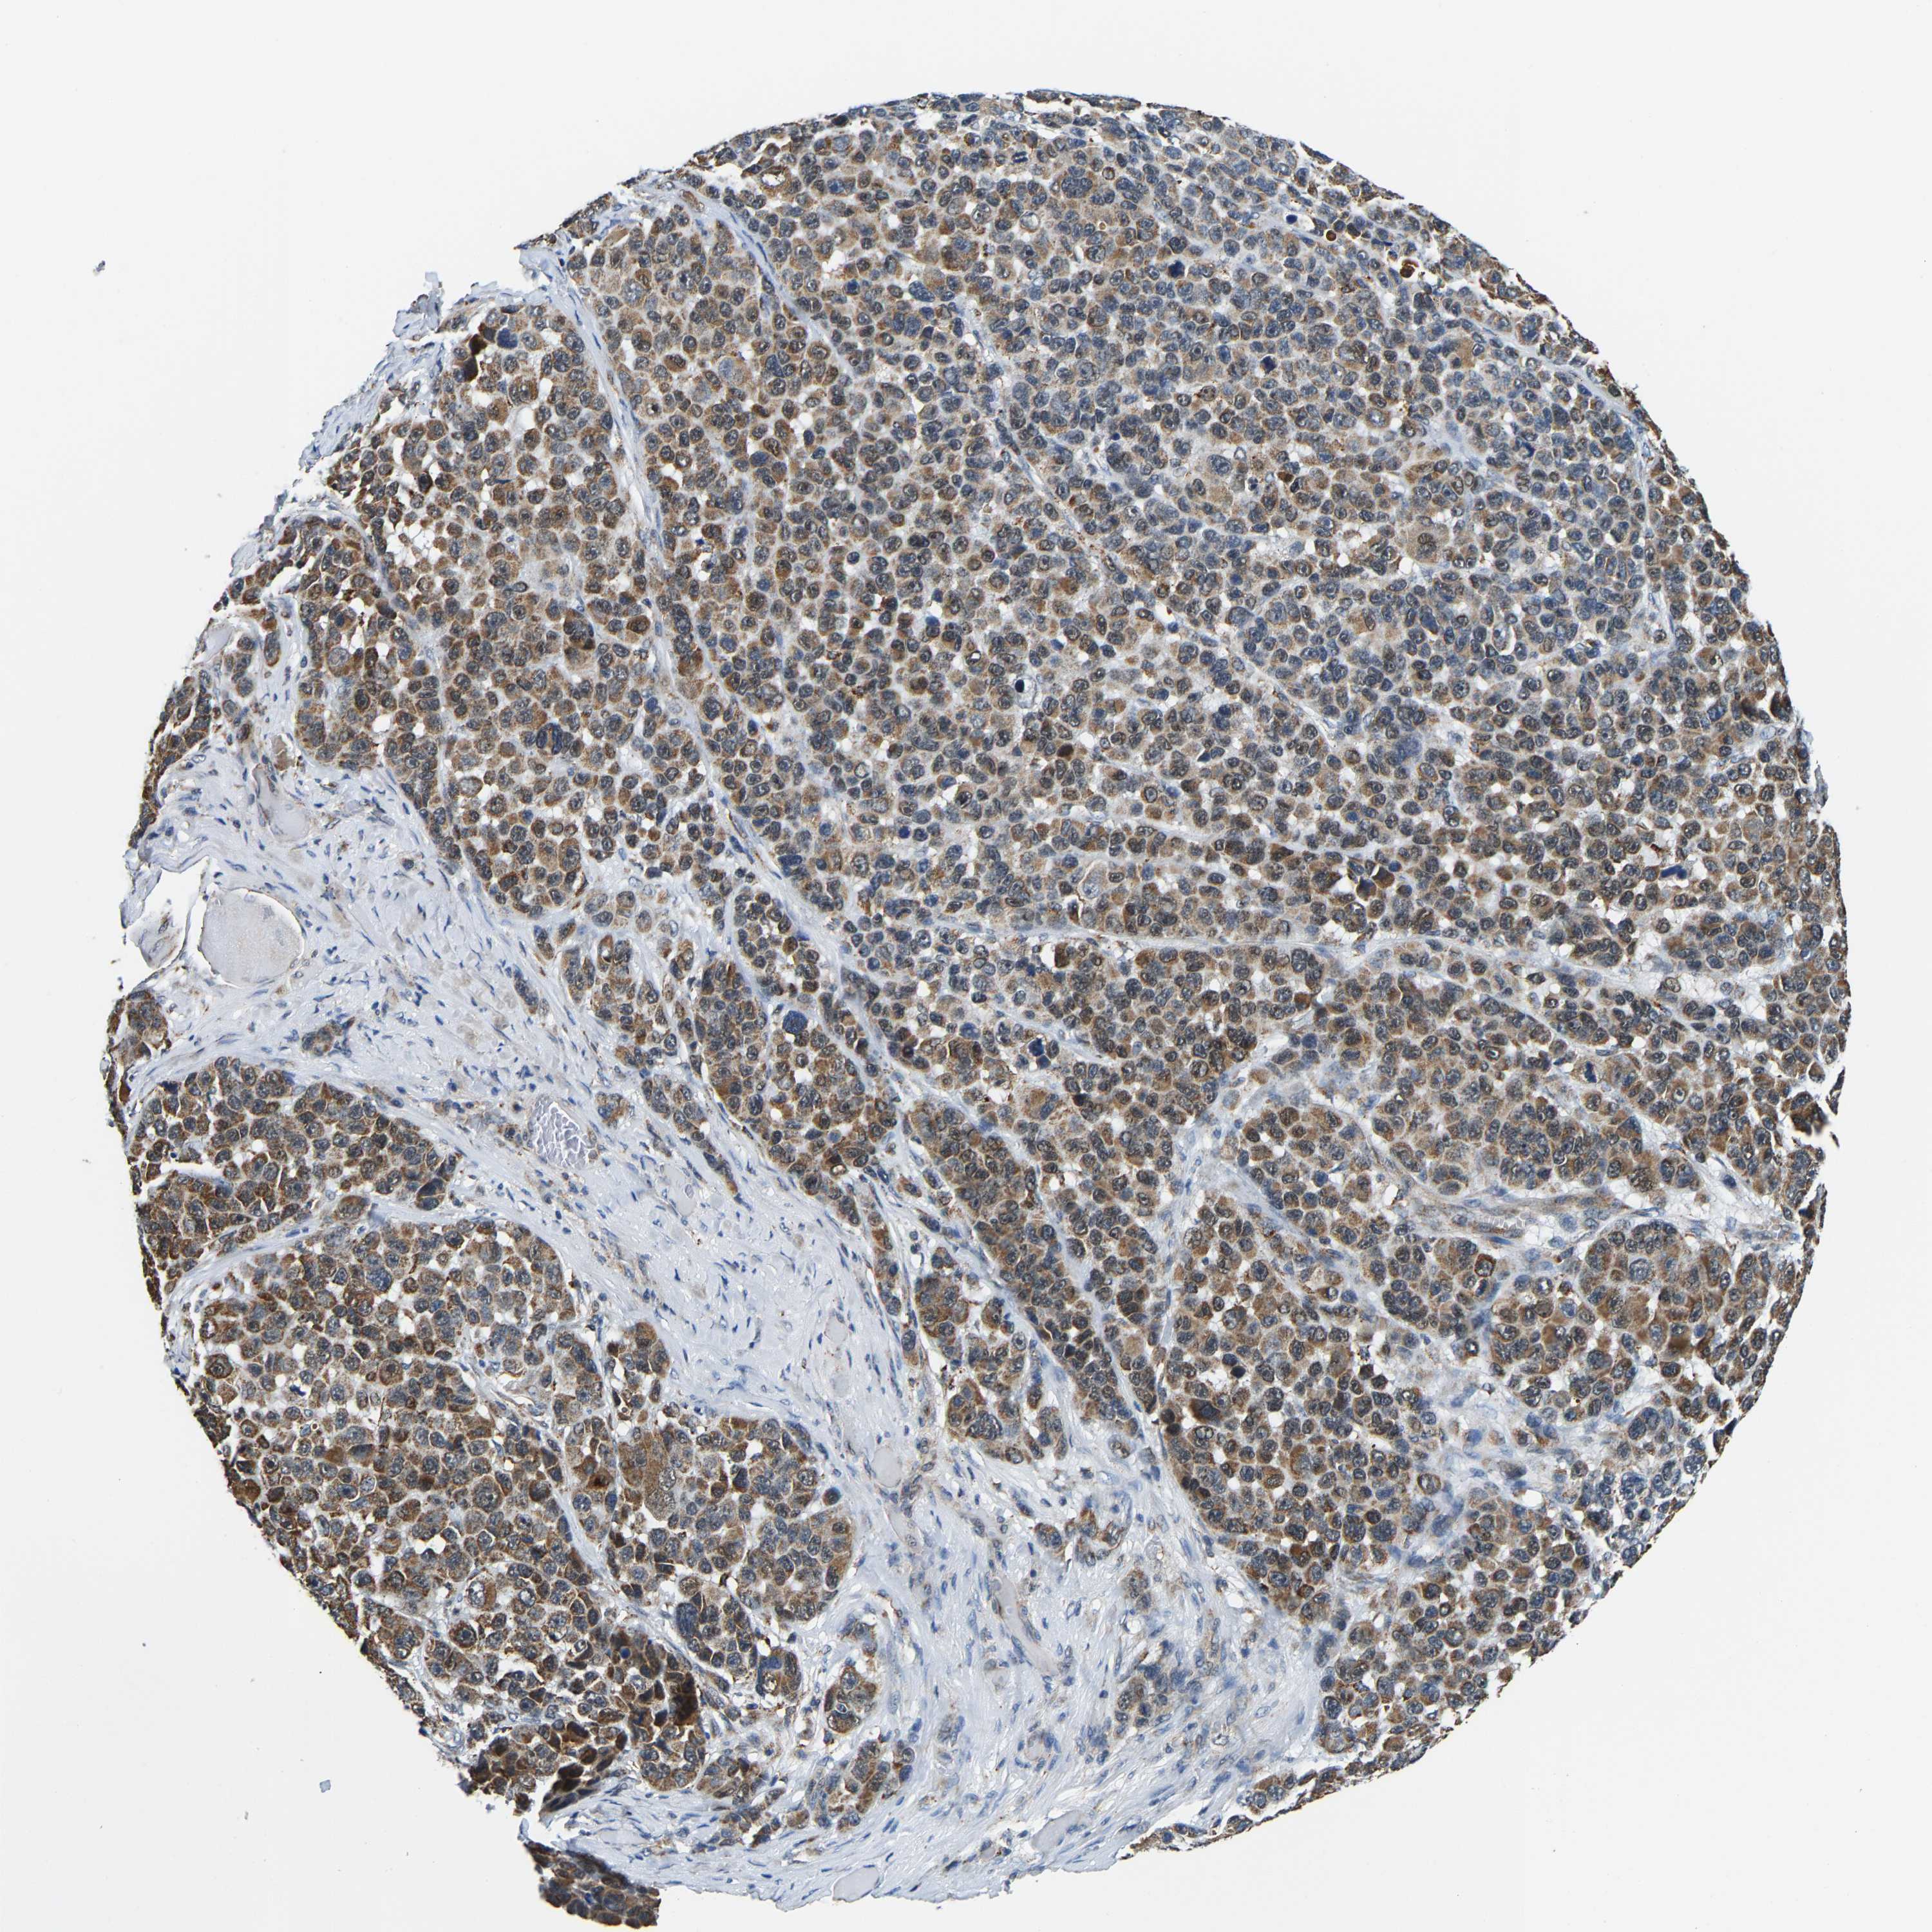

MELANOMA - Protein expressioni

A mouse-over function shows sample information and annotation data. Click on an image to view it in a full screen mode. Samples can be filtered based on level of antibody staining by selecting one or several of the following categories: high, medium, low and not detected. The assay and annotation is described here.

Note that samples used for immunohistochemistry by the Human Protein Atlas do not correspond to samples in the TCGA dataset.

Antibody stainingi

Antibody staining in the annotated cell types in the current human tissue is reported as not detected, low, medium, or high, based on conventional immunohistochemistry profiling in selected tissues. This score is based on the combination of the staining intensity and fraction of stained cells.

Each image is clickable and will lead to virtual microscopy that enables deeper exploration of all samples and also displays staining intensity scores, fraction scores and subcellular localization as well as patient and tissue information for each sample.

Antibody HPA020266

Antibody HPA020268

Staining

High

Medium

Low

Not detected

Intensity

Strong

Moderate

Weak

Negative

Quantity

>75%

75%-25%

<25%

None

Location

Nuclear

Cytoplasmic/membranous

Cytoplasmic/membranous,nuclear

Malignant melanoma, NOS

Malignant melanoma, Metastatic site